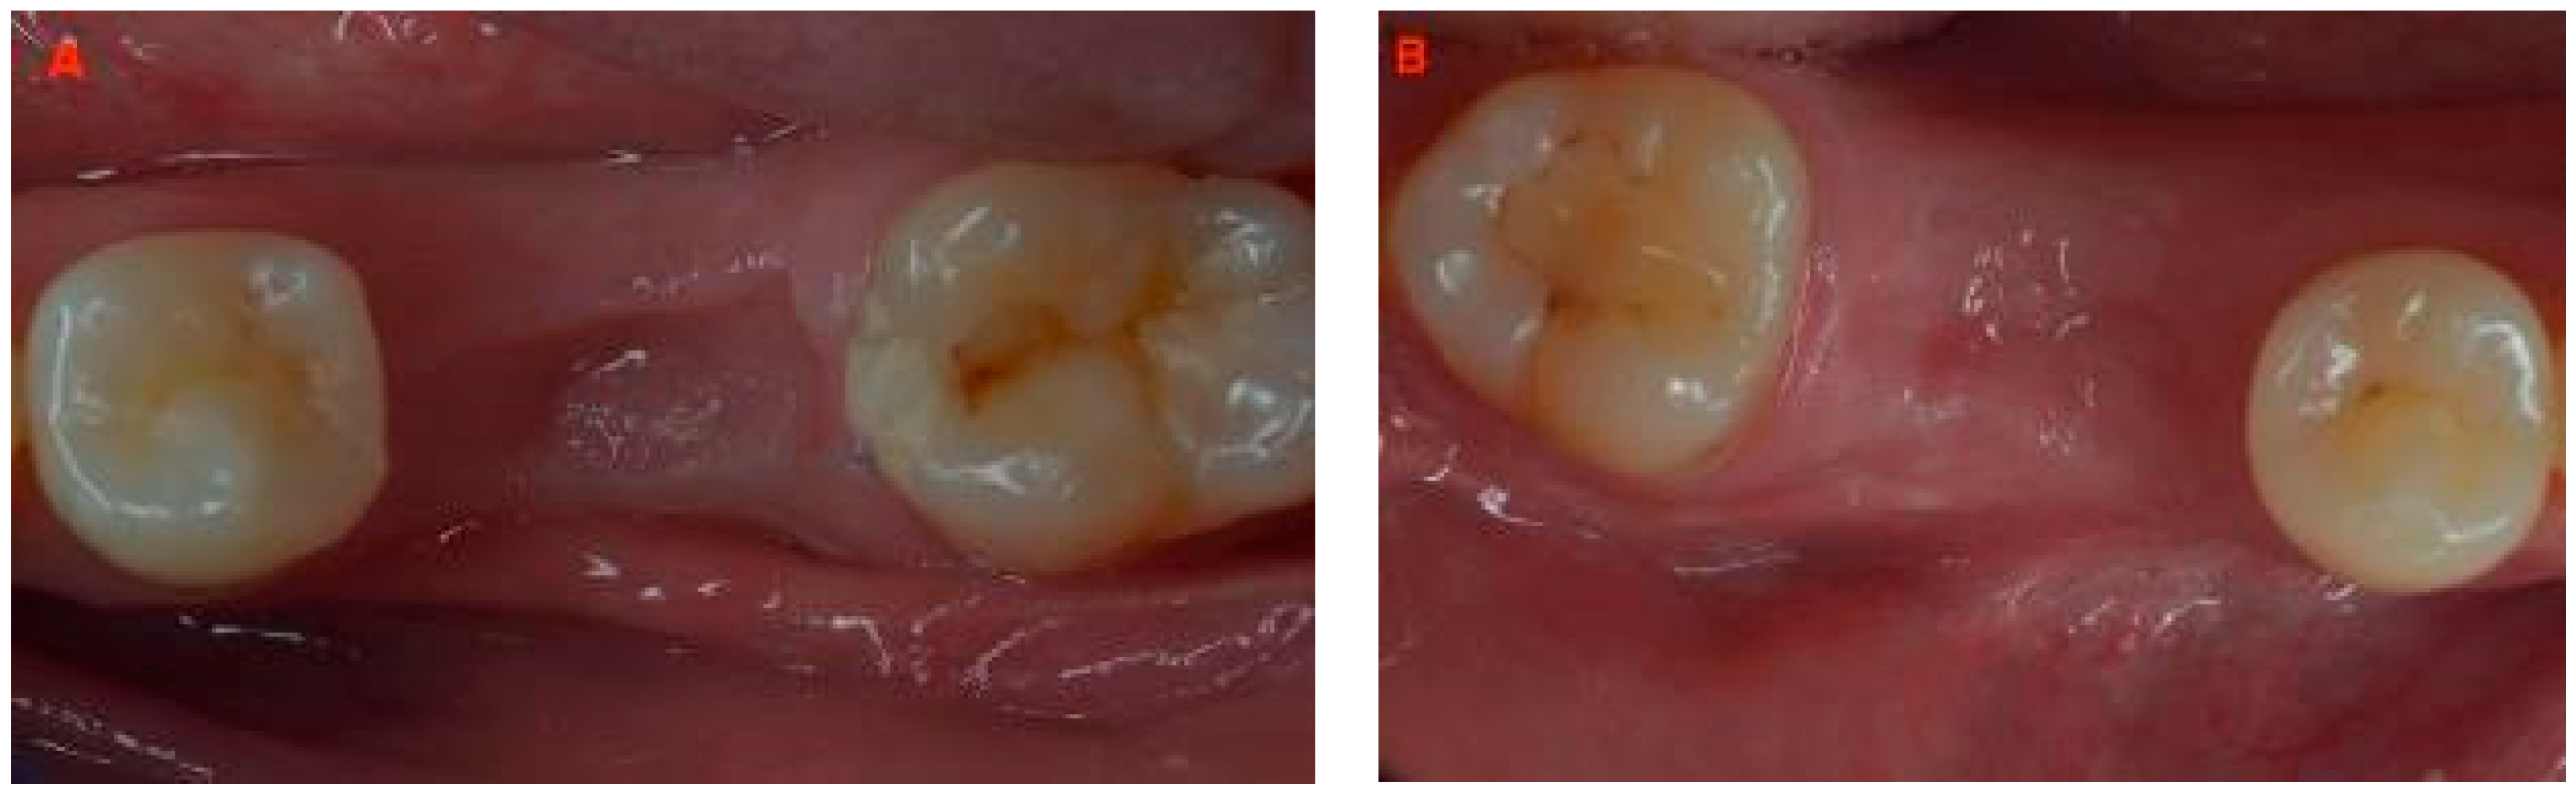

2. Materials and Methods

2.1. Surgical Protocol